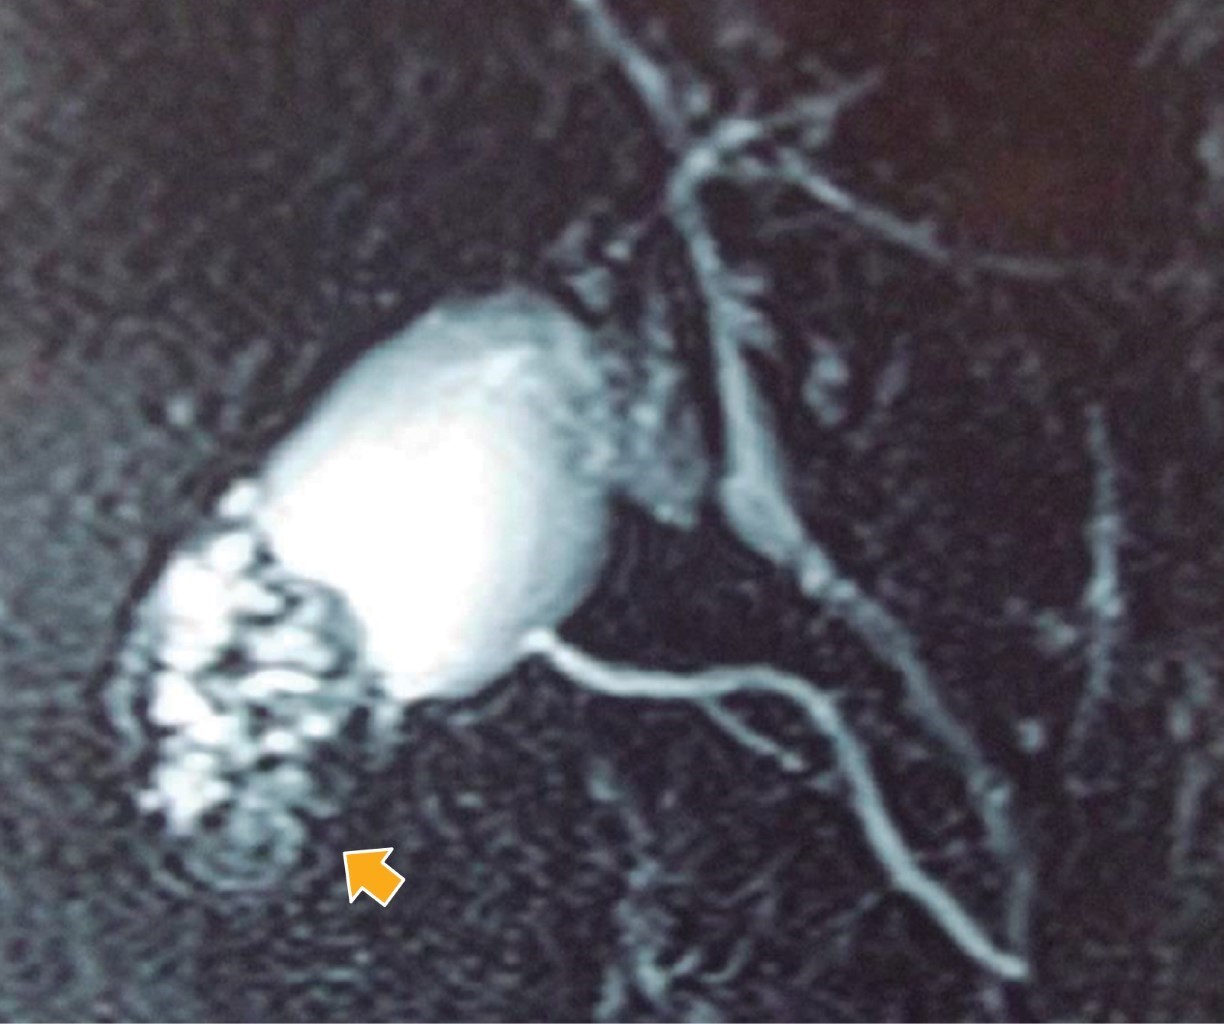

La RMN puede aportar mayor precisión en caso de duda diagnóstica (Figura 2). De hecho, tiene una mayor sensibilidad (73 vs 80.3%) y especificidad (96.3 vs 98.2%) que la ecografía.16 En ella, el engrosamiento de la pared de la VB se puede evidenciar tanto en T1 como en T2. Los senos de RA típicamente aparecen hiperintensos en T2, hipointensos en T1 y no muestran realce de contraste. La conjunción de engrosamiento parietal y divertículos intramurales con el "signo del collar de perlas" distingue la ADM de otras etiologías y se observa en T2 como múltiples cavidades de alta intensidad en la pared vesicular. Este signo es más prominente en la colangio-RMN.21,22

Figura 2